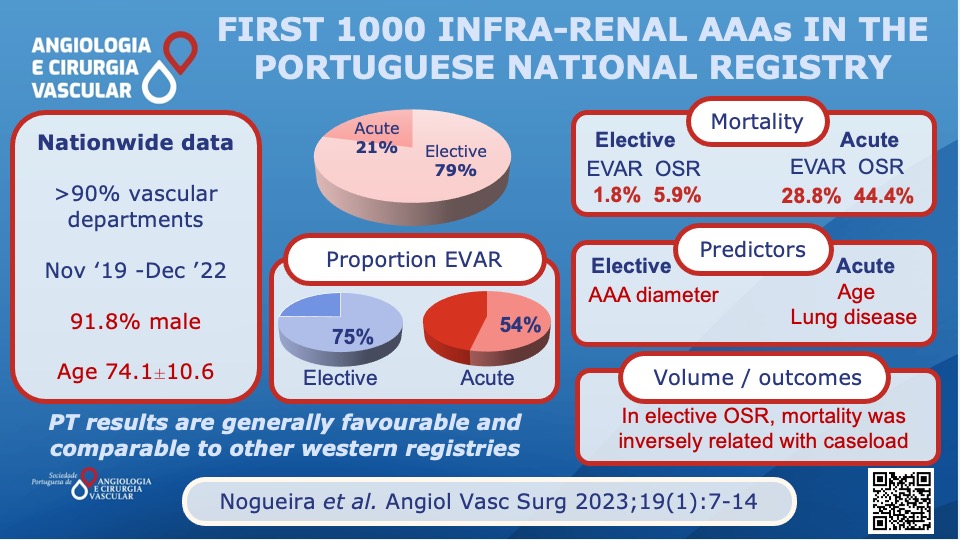

Do you comply with the average time recommended by the guidelines in the treatment of ruptured AAA? Read more about Rato JP et al experience here: acvjournal.com/index.php/acv/… #spacv #rupturedAAA #vascularsurgery Ryan Gouveia e Melo ESVS Society for Vascular Surgery Vascular News